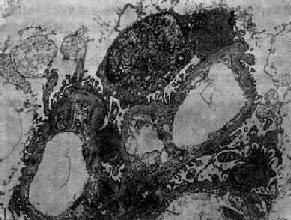

图12-9 毛细血管内增生性肾小球肾炎

电镜下见驼峰状沉积物位于毛细血管基底膜表面。沉积物表面有上皮细胞覆盖,上皮细胞足突消失